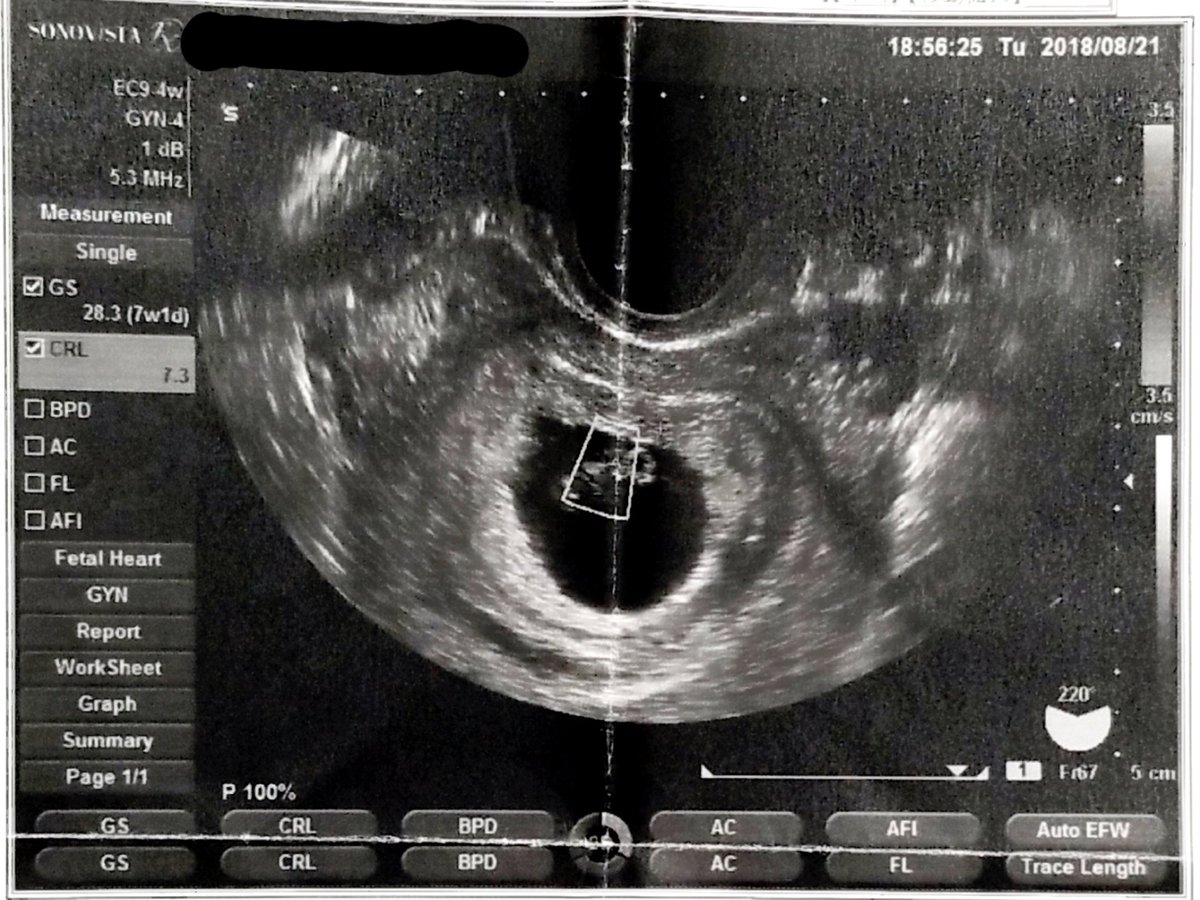

2018.8.21 流産宣告から1週間。 あれから出血も腹痛もなく健診の日が来たためクリニックへ。 そこで見たものは… #育児漫画 #育児日記 #妊娠 #妊娠初期 #心拍確認 #エコー #妊娠2ヶ月 pic.twitter.com/MZRqLfdoJX

2019-08-15 21:16:13 拡大

拡大

拡大

拡大